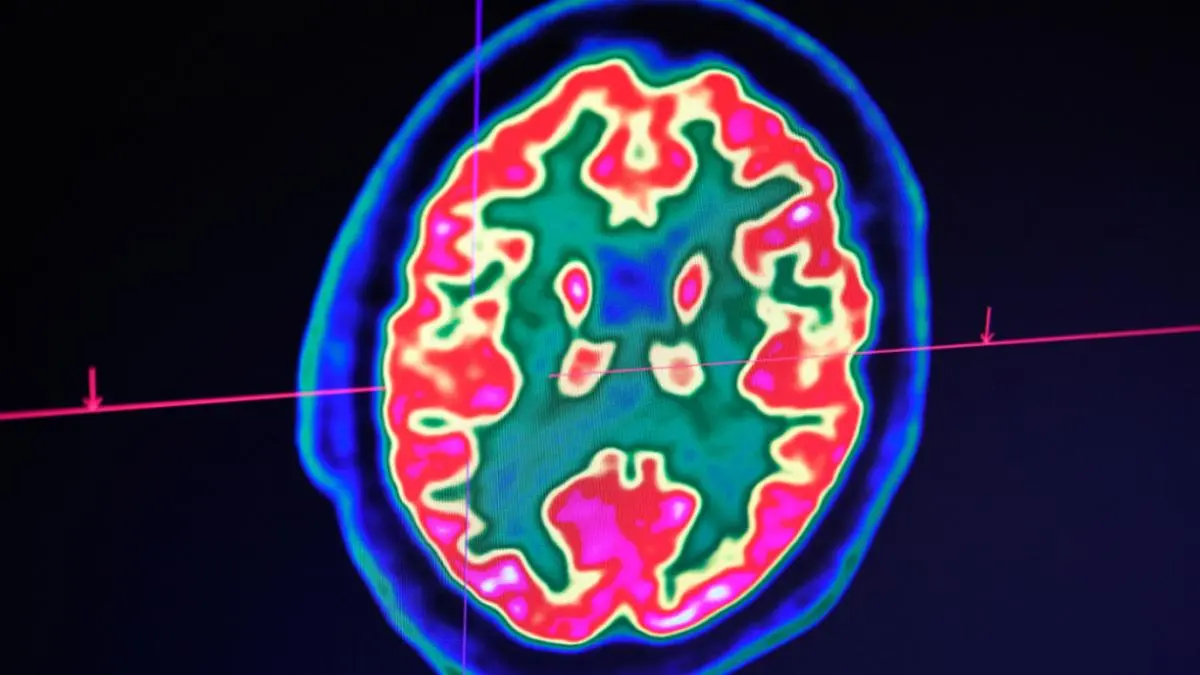

Stammzellen können Hirn nach Schlaganfall heilen

Forschenden ist in Zürich nach eigenen Angaben ein Meilenstein für die Therapie von Hirnerkrankungen nach Schlaganfällen gelungen. Ihre Studien zeigten, dass neuronale Stammzellen Schlaganfall-Schäden im Mäusehirn rückgängig machen können. Einer von vier Erwachsenen erleide im Laufe seines Lebens einen Schlaganfall. Es sei darum essenziell, neue therapeutische Ansätze für eine mögliche Hirnregeneration nach Krankheit oder Unfall zu verfolgen, hieß es.